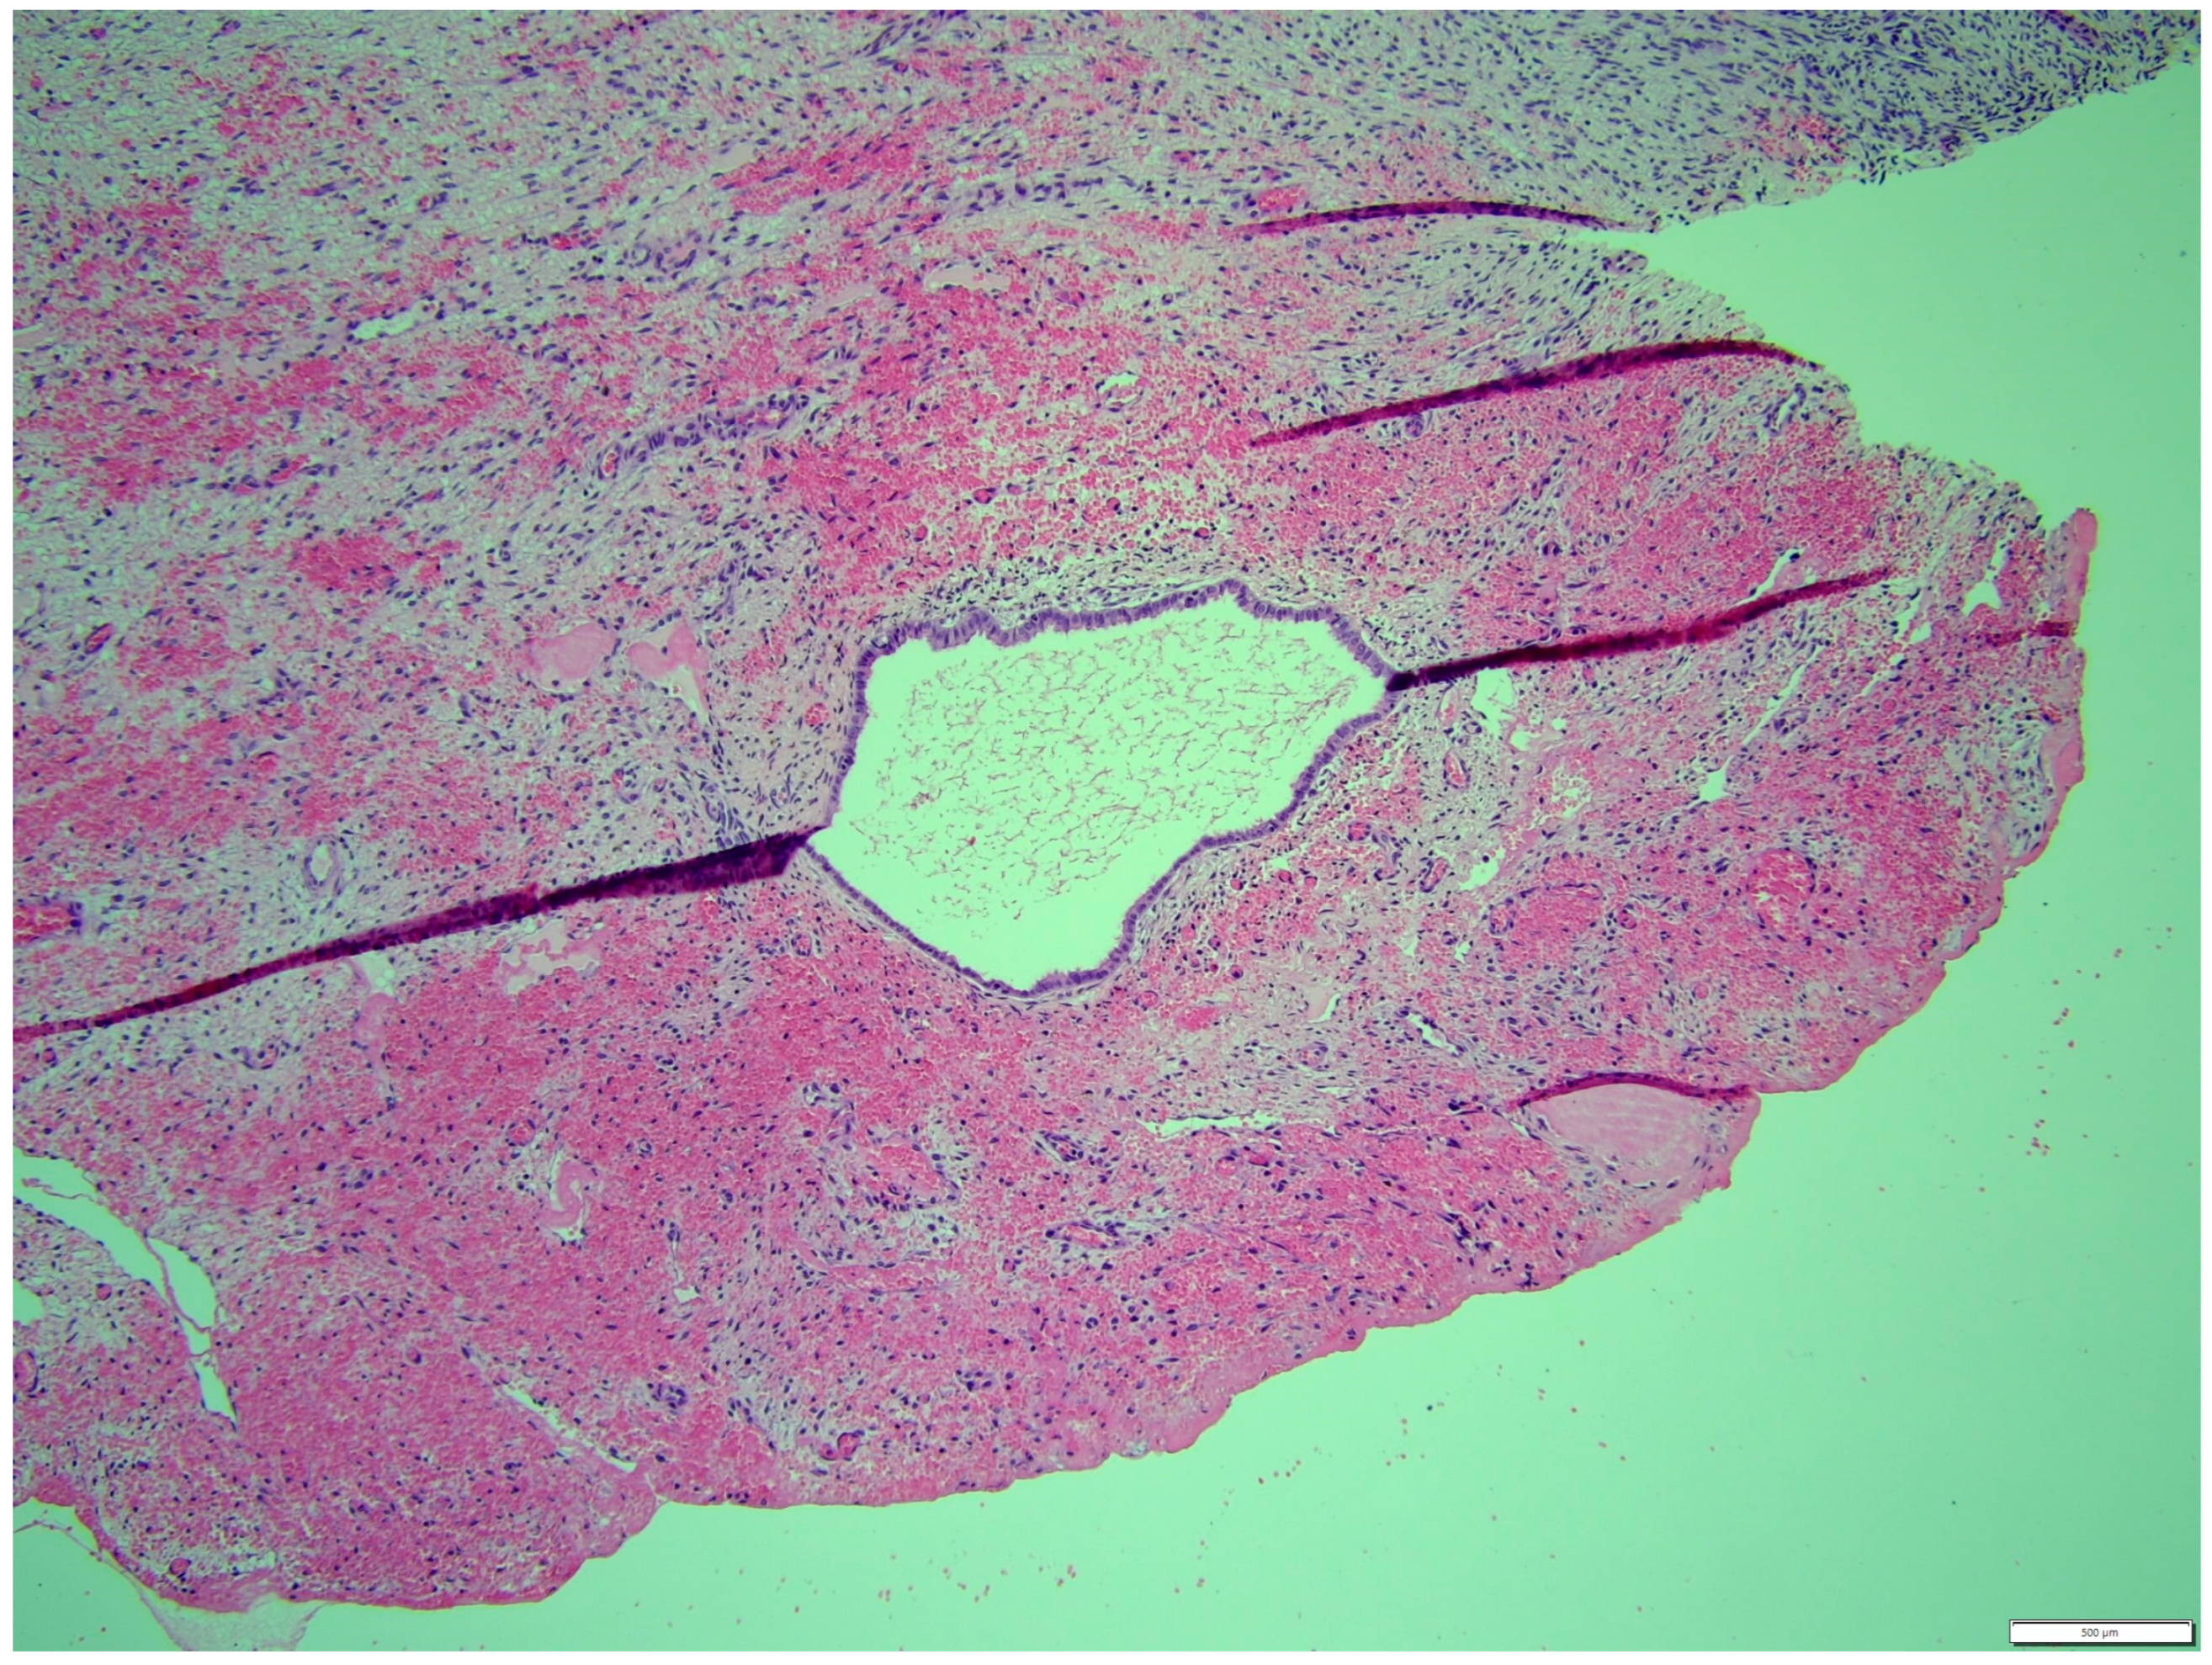

Histologically, both tumor areas were distinctly different from each other (Figure 7 and Figure 8). In the obtained sample for histological examination, the portion of the thecoma was significantly lower (Figure 9). Marked hemorrhage (but not blood-filled lacunae) and very sparse granulation-type connective tissue were observed at the border between both tumor tissues (Figure 10). Hemorrhagic blood masses infiltrated a larger part of the thecoma tissues. A single cystic structure lined with columnar epithelium was found in the hemorrhagic zone, with a very sparse amount of mucus-like material in the lumen (Figure 11).

Figure 7. Distinction between fibroma and thecoma parts. HE, 100× magnification.

Animals 14 01307 g007